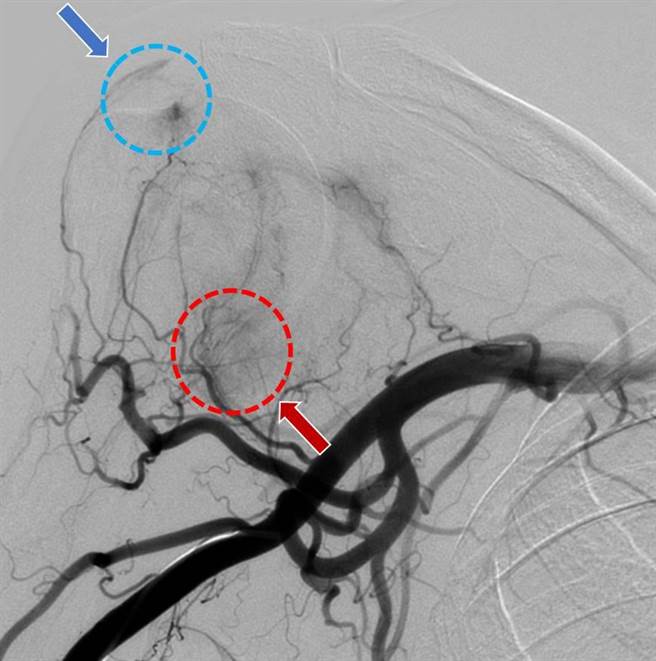

肩膀关节血管摄影检查:圆圈内显示发炎处毛毛样血管增生,异常血管增生处也对应到疼痛位置。(部苗医院提供/李京升苗栗传真)

龚先生一开始先接受注射治疗,但只有部分缓解,经过讨论后,决定进行微细动脉栓塞止痛术。徐庸说,这个手术只需要局部麻醉,在手腕部位的动脉进行穿刺,将微导管伸入肩膀疼痛部位血管,利用血管摄影的指引下注射显影剂,找出异常增生的小血管,再通过微导管注入栓塞药物,以去除这些引起疼痛的异常小血管,进而改善发炎和异常血流,一般治疗时间约需要1至2小时。